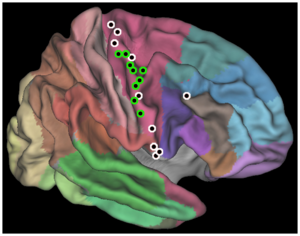

- 5.3 Rapid and Efficient Localization of Depth Electrodes and Cortical Labeling using Free and Open Source Medical Software in Epilepsy Surgery Candidates